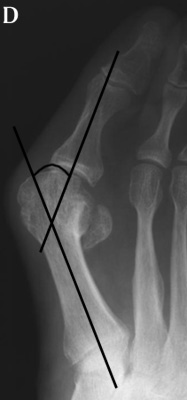

25º, C. moderate when HAV is 26º to 35º, and severe (D) when HAV is greater than

35º.